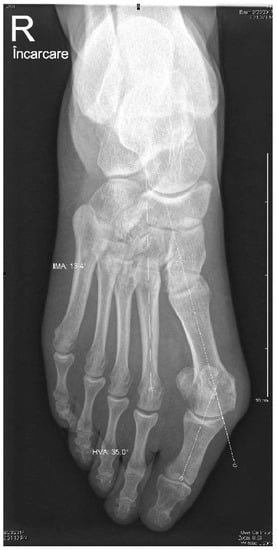

We also radiologically evaluated each patient using standard weight-bearing anteroposterior and lateral images of the foot (Figure 1 and Figure 2). The HVA and IMA angles were preoperatively measured using Cedara I-View 6.3.3. At 6 weeks, 6 months, and 12 months, we performed additional radiological images to evaluate the angle modifications.

Figure 2. Preoperative lateral weight-bearing image.